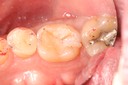

Alan Chinn #2 & 5 pre-op